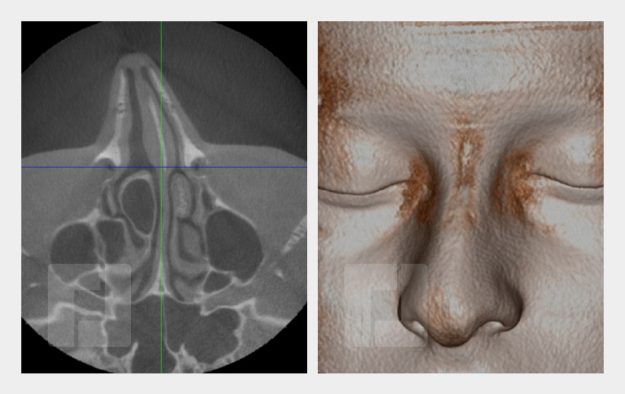

Beispiele

Durch Öffnen der Bildergalerie haben Sie die Möglichkeit selber durch die Beispiele zu navigieren.